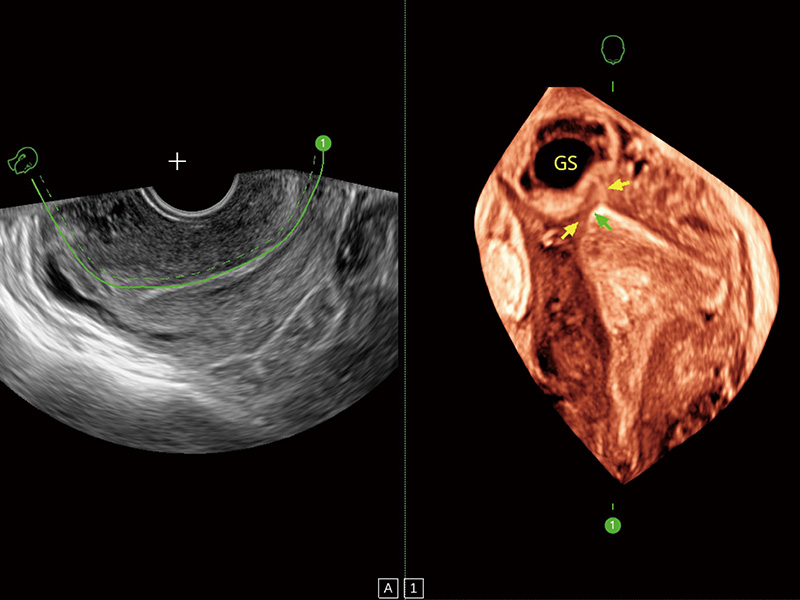

“生育问题”即关系民族复兴,也关系亿万家庭的幸福。随着婚育年龄推迟、社会压力增加等因素,越来越多人群也面临着“生不出、生不好”的问题。辅助生殖作为治疗不孕不育最有效的方法之一,也逐渐成为育儿新希望。而超声检查能为生殖需求人群的初诊评估提供宝贵的信息。 P20 Elite是球速体育入口匠心打造的一款生殖应用型彩超。她继承球速体育入口高端极光平台,突破性地将多款新型芯片及硬件模块进行整合,均衡了高端系统性能与小巧灵动机身。P20 Elite卓越的图像质量搭载专科探头,旨在为您提供全面的辅助生殖解决方案。

P20 Elite配备了丰富的生殖探头群和临床应用功能,在卵泡监测、穿刺取卵、胚胎移植、妊娠确认等领域,为生殖需求人群提供了新的临床机会,重新定义高端超声如何应用于生殖健康检查。